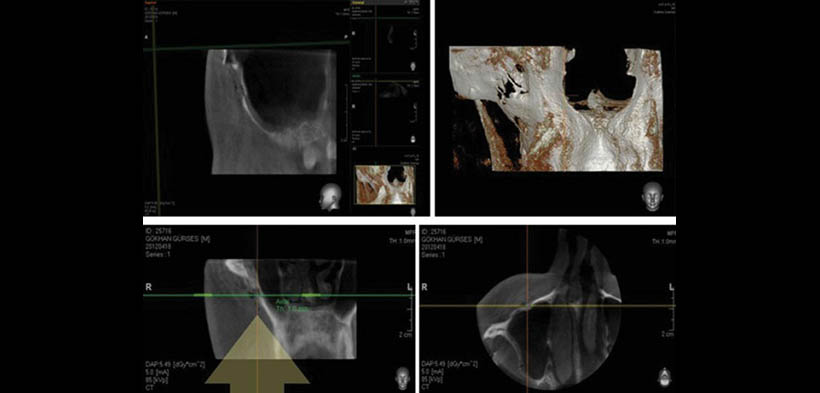

El trauma maxilofacial causa problemas clínicos graves, debido a las características anatómicas de la región. Las imágenes en 3D es esencial para la localización de los componentes anatómicos y patológicos y puede proporcionar puntos de vista de los tejidos tanto duros como blandos, mientras que las proyecciones 2D son de uso limitado debido a la superposición, la ampliación, la distorsión y tergiversación de estructuras. Muchos estudios han examinado la exactitud geométrica de CBCT y han llegado a la conclusión de que la tecnología hace posible inspeccionar la topografía ósea 3D y estructuras vitales adyacentes con gran precisión. El principal desafío para la CBCT de imágenes es la falta de familiaridad con el concepto de imagen multiplanar experimentado por la mayoría de los profesionales de la odontología, lo cual representa un enorme reto el poder familiarizarlos y hacer que lo acepten y den el uso que corresponde. A continuación se muestra un caso de la aplicación de la CBCT en el diagnóstico de fractura del seno maxilar (fig.1-3)(1).

Fig. 3. CBCT. Línea de fractura no fragmentada en la pared anterior del seno maxilar.